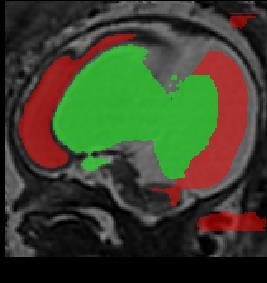

Limiting failures of machine learning systems is of paramount importance for safety-critical applications. In order to improve the robustness of machine learning systems, Distributionally Robust Optimization (DRO) has been proposed as a generalization of Empirical Risk Minimization (ERM). However, its use in deep learning has been severely restricted due to the relative inefficiency of the optimizers available for DRO in comparison to the wide-spread variants of Stochastic Gradient Descent (SGD) optimizers for ERM. We propose SGD with hardness weighted sampling, a principled and efficient optimization method for DRO in machine learning that is particularly suited in the context of deep learning. Similar to a hard example mining strategy in practice, the proposed algorithm is straightforward to implement and computationally as efficient as SGD-based optimizers used for deep learning, requiring minimal overhead computation. In contrast to typical ad hoc hard mining approaches, we prove the convergence of our DRO algorithm for over-parameterized deep learning networks with ReLU activation and a finite number of layers and parameters. Our experiments on fetal brain 3D MRI segmentation and brain tumor segmentation in MRI demonstrate the feasibility and the usefulness of our approach. Using our hardness weighted sampling for training a state-of-the-art deep learning pipeline leads to improved robustness to anatomical variabilities in automatic fetal brain 3D MRI segmentation using deep learning and to improved robustness to the image protocol variations in brain tumor segmentation. Our code is available at https://github.com/LucasFidon/HardnessWeightedSampler.